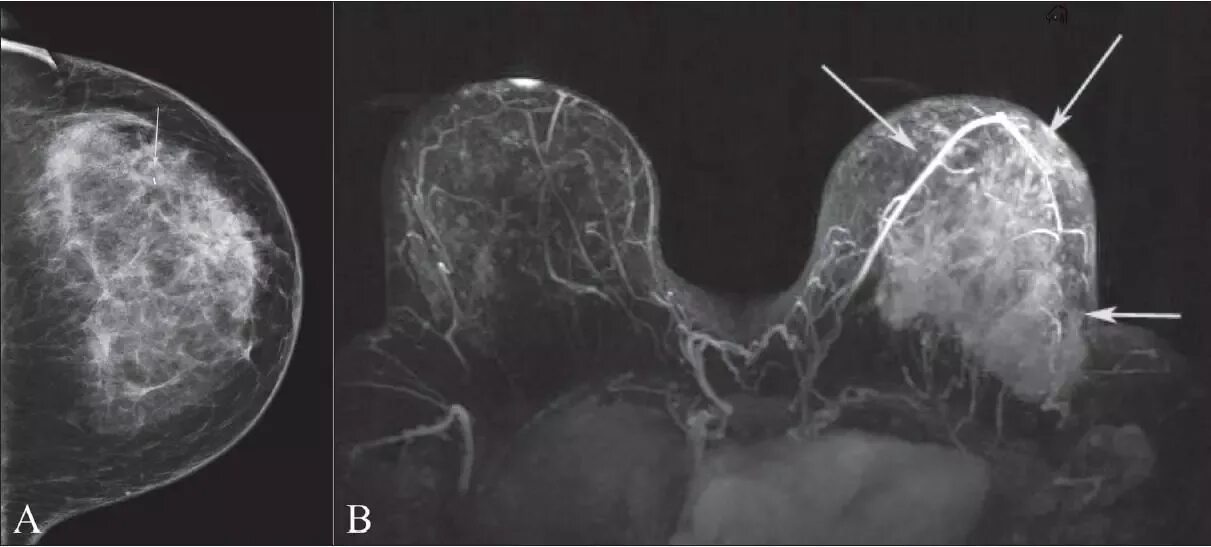

Делают ли мрт молочных желез